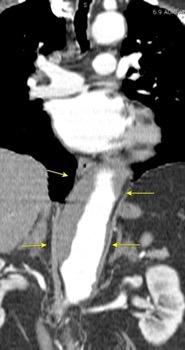

Paciente que ingresa con síntomas de colecistitis aguda. Antecedentes de trauma importante muchos años antes

Zhao L et al. Delayed traumatic diaphragmatic rupture: diagnosis and surgical treatment. © Journal of Thoracic Disease.

J Thorac Dis 2021

Asas

Líquido pericolecistítico

V. biliar con cálculos

Diafragma